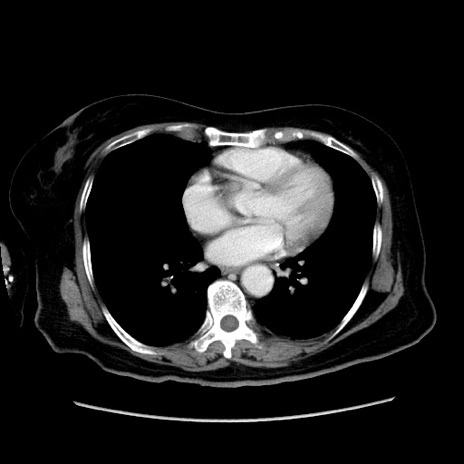

症例19(横断像)

【症例】80歳代女性

【主訴】下腹部痛

【現病歴】約8時間前より下腹部痛の出現あり、救急外来受診。

【既往歴】両側付属器切除

【身体所見】意識清明、下腹部正中に手術痕あり、その部位に一致して圧痛と反跳痛あり。腸蠕動音は亢進。

【データ】WBC 9300、CRP 0.15